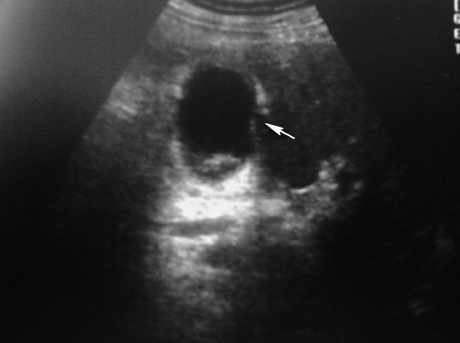

Желчный пузырь с неравномерно утолщённой стенкой на всём протяжении . Дифференцировка слоёв отсутствует ...

Диагноз подтвержден "операционно"...

Еще так

Таки, наверное, да, только скопление жидкости , скорее всё - таки паравезикальноSerg писал(а):острый холецисти с перфорацией, определяется дефект стенки и скопление жидкости в паренхиме печени

Да, все верно. Только в просвете еще и конкременты (может снимок не совсем удачный, больше хотелось вывести "дырку" в стенке, а не камень, но он был

Кстати нарушение целостности видно и здесь: Послеоперационный диагноз (списала с истории болезни): ЖКБ.Острый калькулезный гангренозный холецистит. Перфорация желчного пузыря. Местный перитонит.